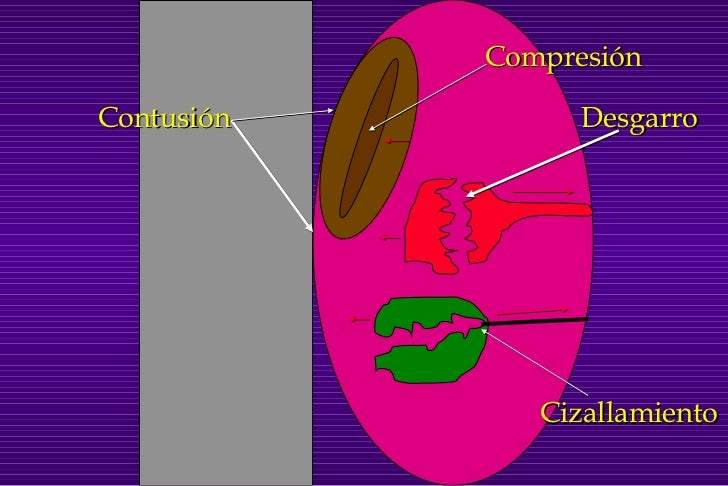

trauma cerrado: las fuerzas que actúan son 3 tipos:

comprensión

las células son comprimidas y aplastadas lesionando los tejidos y órganos

desaceleración

se presenta en órganos unidos a otras estructuras que al momento del impacto presentan movimientos diferentes.

sobrepresión

se presenta cuando un órgano cavitado es comprimido a un ritmo muy rápido en comparación con el tejido circundante